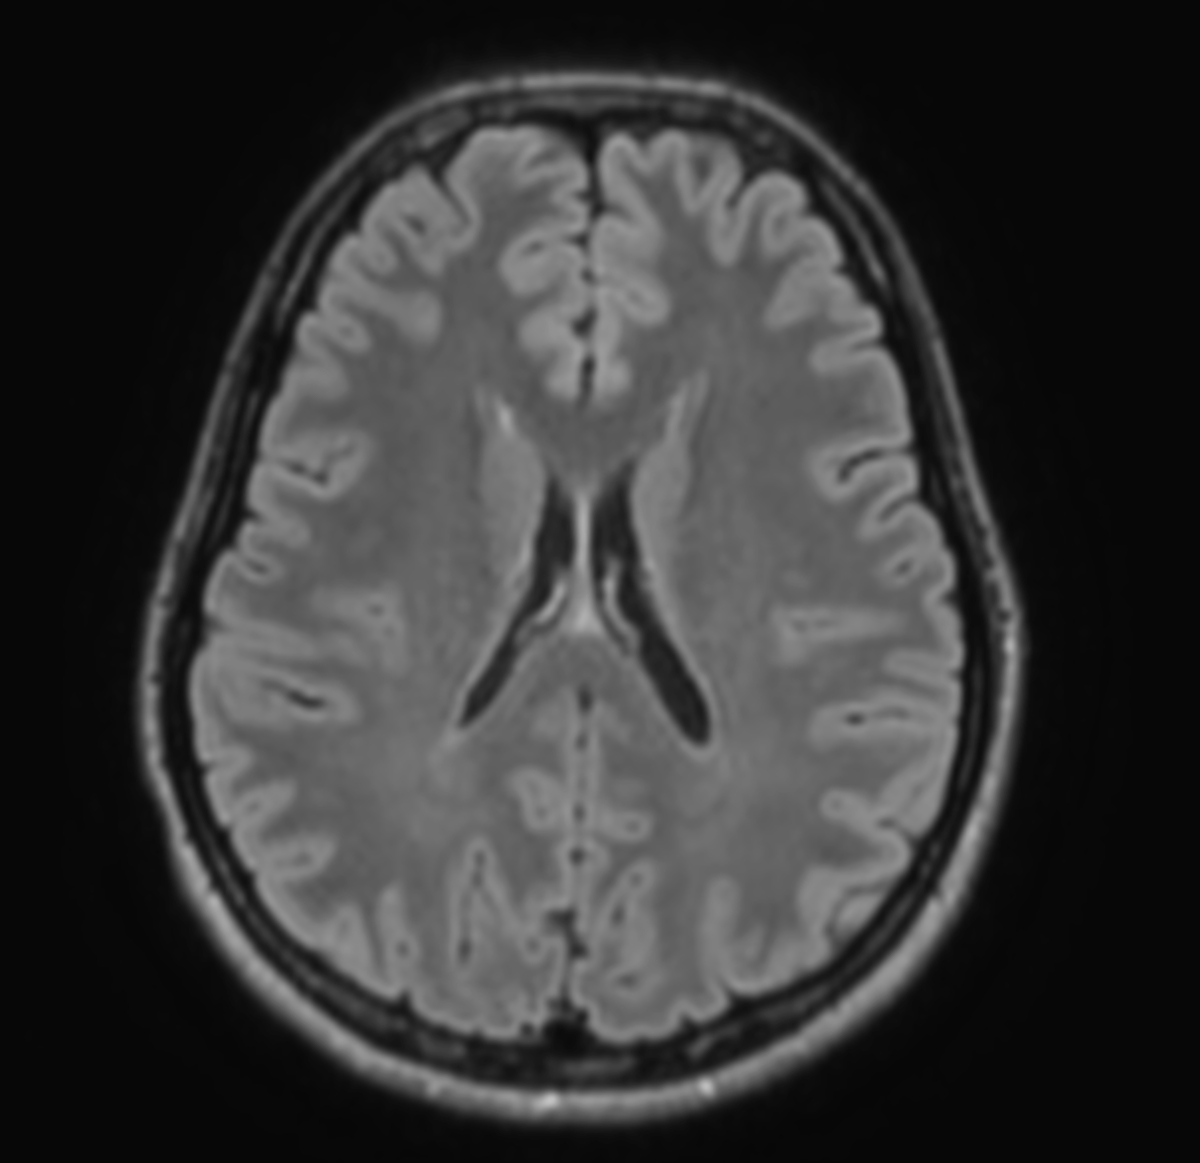

Вот как рентгенолог представляет себе человека со здоровым головным мозгом

И не зря данные картинки всплывают у меня в голове – это аксиальные срезы головного мозга, которые получены с помощью МРТ. (если хотите узнать , что такое "аксиальные срезы" - вам сюда!) На медицинском языке эти изображения правильно называются " МР-томограммы".

А теперь внимательнее посмотрим на наши изображения. На первой картинке борозды узкие, извилины широкие, белое вещество однородное - это норма. А на второй картинке все наоборот - желудочки широкие, борозды широкие, извилины узкие, а в белом веществе видны многочисленные очаги. Именно в этих отличиях между томограммами и кроются различия в ментальных статусах пациентов, о которых я говорил ранее. Итак по порядку:

1. Что это за очаги? Эти очаги возникают, когда кровоснабжение головного мозга начинает ухудшаться. Причем не на уровне крупных сосудов - в этом случае возникает ишемический инсульт. Инсульт возникает остро и внезапно со всеми своими разнообразными последствиями вплоть до отсутствия возможности передвигаться и самостоятельно себя обслуживать. В нашем случае речь о нарушениях микроциркуляции. Здесь же страдают сосуды самого мельчайшего калибра , и в веществе мозга возникают небольшие очаги плохого кровоснабжения или ишемии. Это как бы микроинсульты, но вялотекущие, развиваются годами. В конечном счете в данных очагах нейроны погибают и замещаются рубцовой тканью, неспособной осуществлять нервную деятельность. Каждая зона головного мозга ответственна за какую либо сферу нашей жизнедеятельности: память, эмоции, настроение, двигательная сфера и т.п. Если в данной зоне гибнут нервные клетки - то в клинической картине будут возникать соответствующие симптомы - вялость, апатия, ухудшение памяти, головокружение, нарушения координации и моторики и еще множество других расстройств. В неврологии данные процессы объединены в одно заболевание, которое называется "дисциркуляторная энцефалопатия" или "хроническая ишемия головного мозга". Также, есть ещё более точный медицинский термин "церебральная микроангиопатия" - он отражает не столько клинику, сколько патофизиологические процессы, которые происходят в данных очагах. У этого заболевания тоже есть стадии, и, не вдаваясь в сложные классификации и подробности, зависимость здесь следующая – больше очагов – больше симптомов, меньше очагов – меньше симптомов. Пациенты на последних стадиях могут потерять способность нормально мыслить, передвигаться и обслуживать себя.

2. На первом изображении борозды узкие, а ликвор между извилинами практически не виден. На втором изображении ликвор свободно затекает в борозды между извилинами , так как борозды значительно расширены. Что в этом плохого? Помните , я говорил, что природа изобрела извилины головного мозга для того, чтобы увеличить объём серого вещества? За счет серого вещества мы мыслим и чувствуем. Если мы посмотрим на нормальный здоровый мозг подростка - такое впечатление, что места для ликвора в полости черепа нет вовсе! Вся черепная коробка туго забита нейронами, а борозды шириной всего 1-2 миллиметра - и это прекрасно - мозг растет , развивается и впитывает информацию!